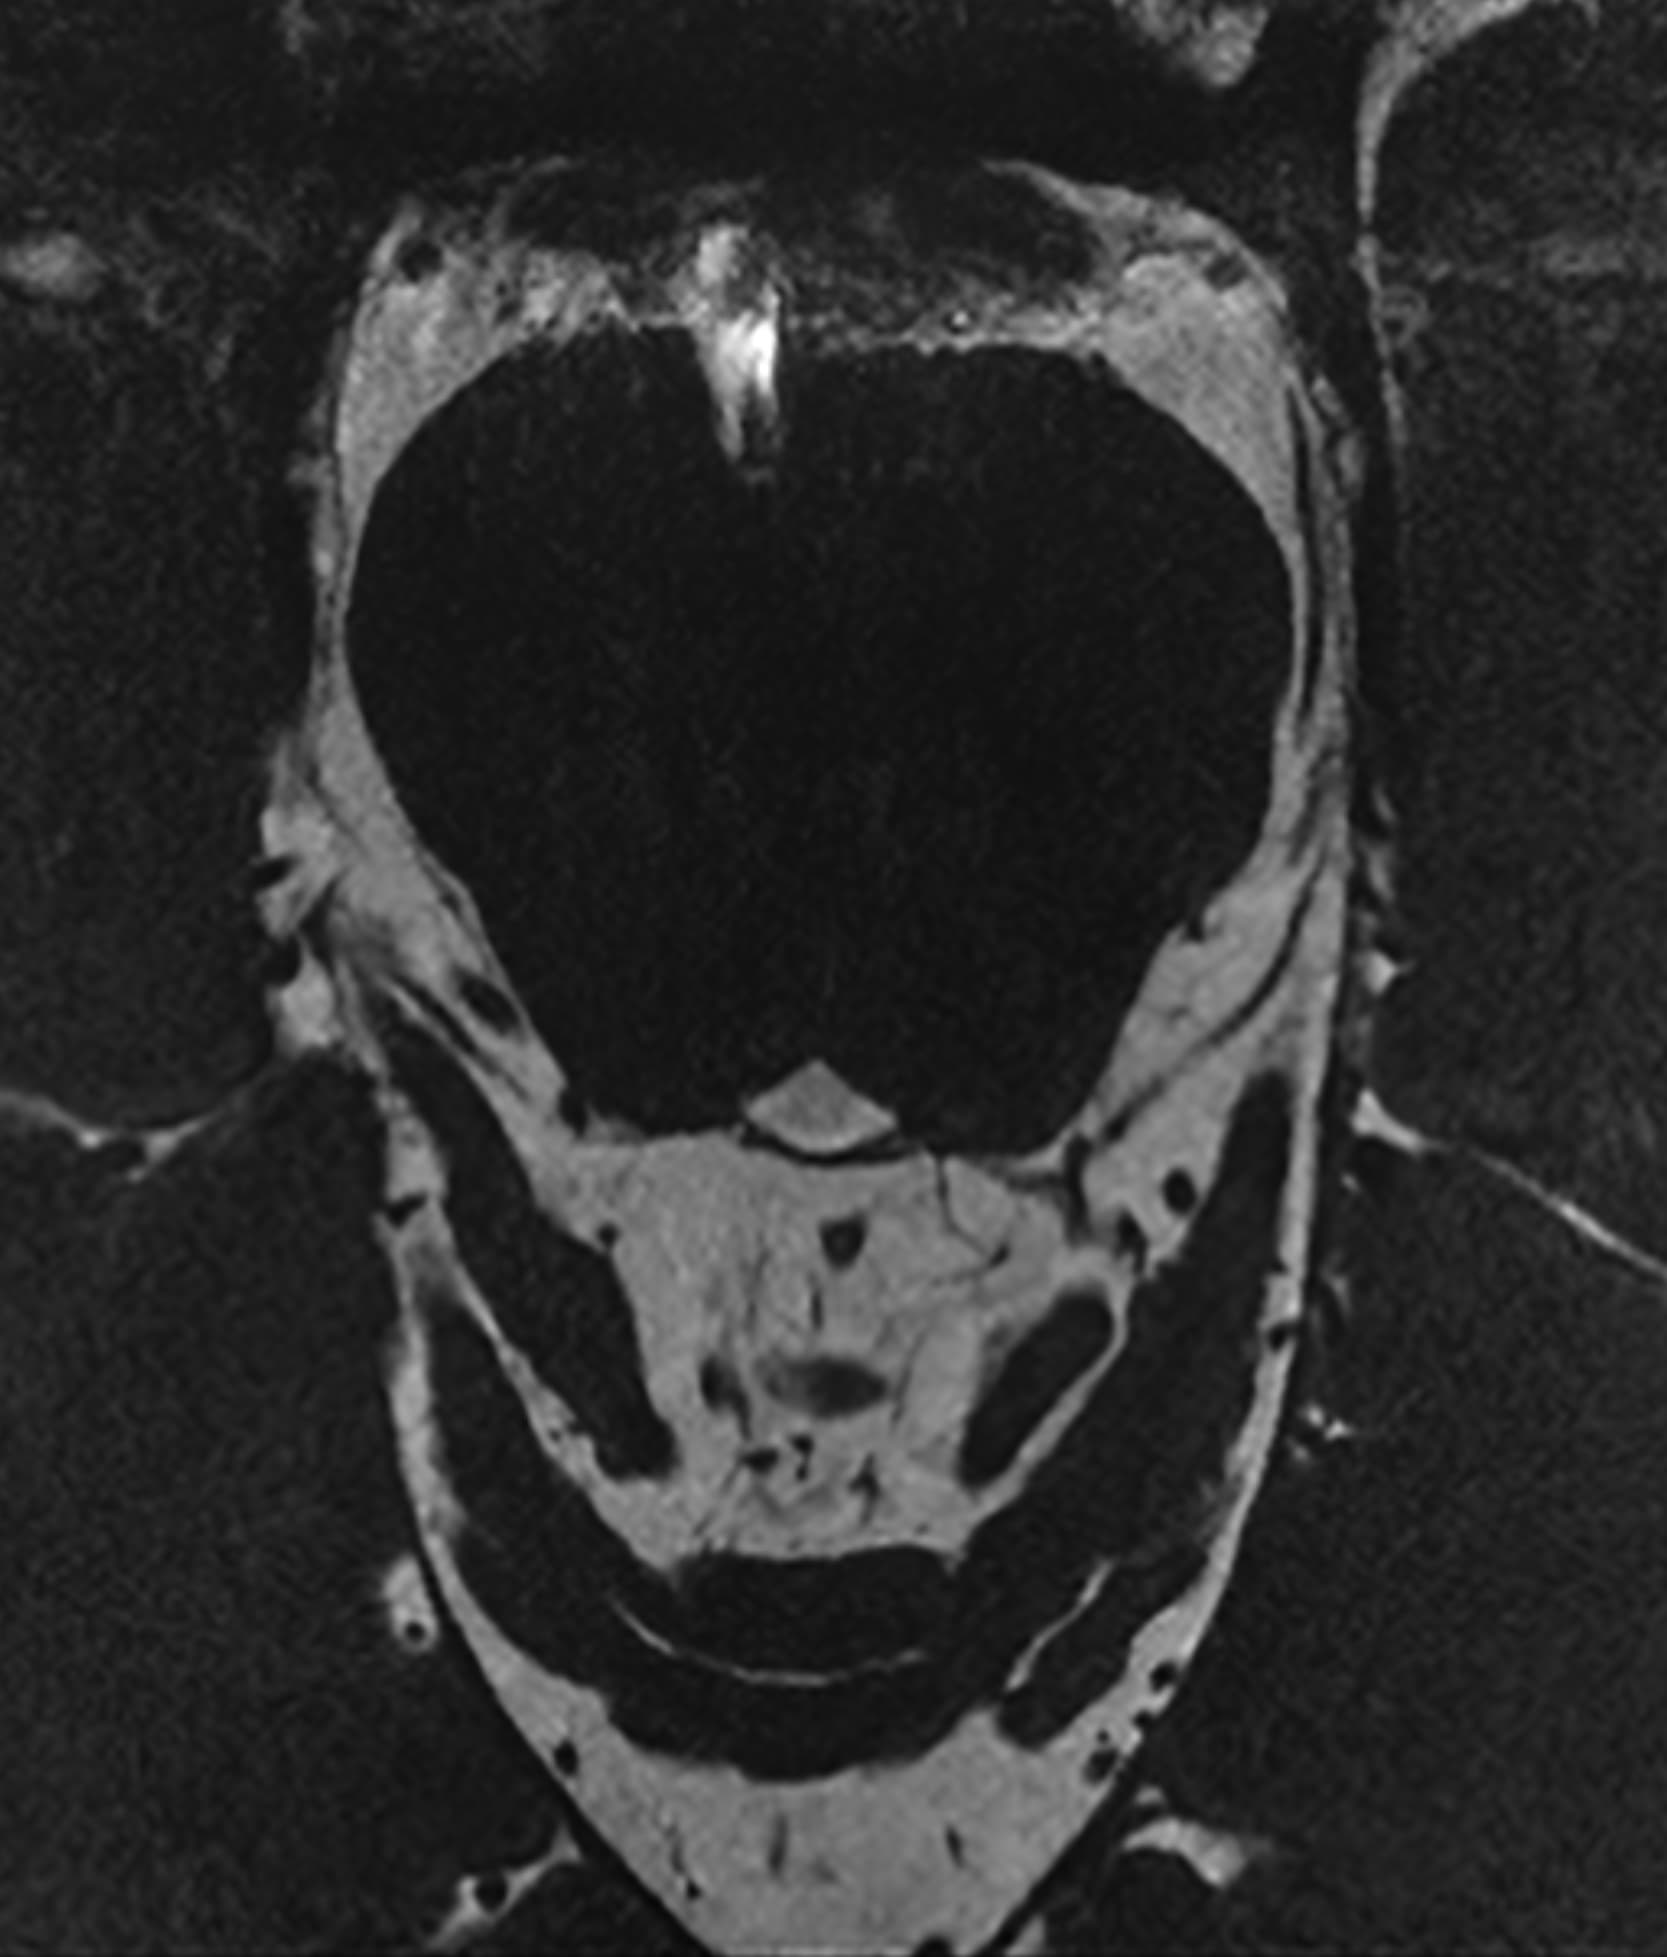

See real-world examples of SwiftMR™ across various MRI systems and anatomical regions

Scan time 03:08

Scan time 1:12